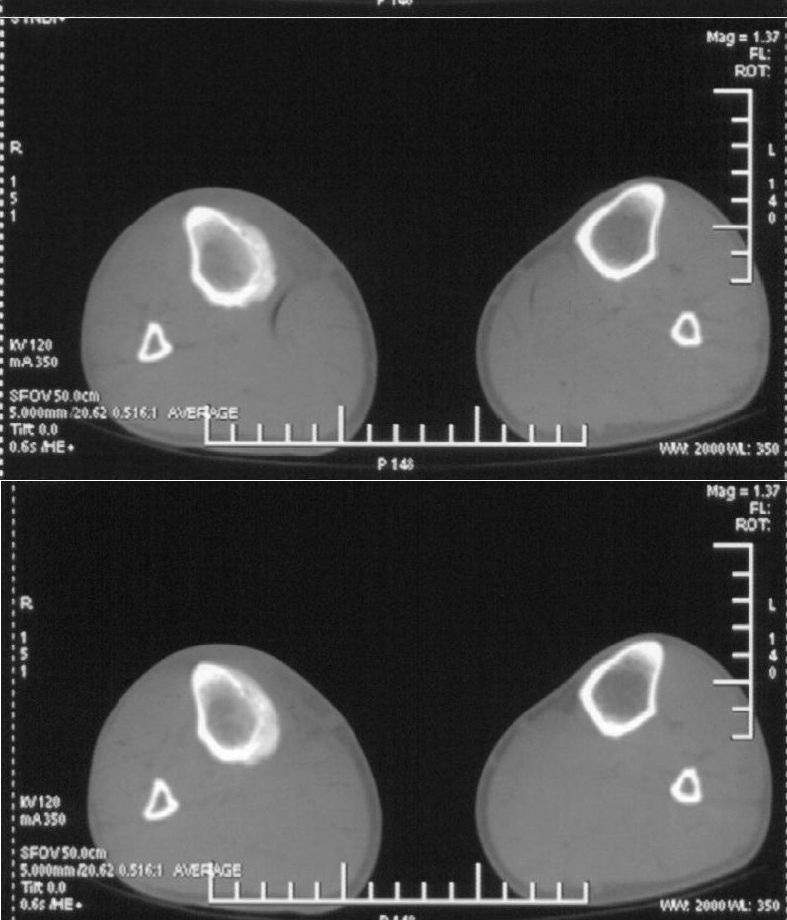

男,42岁。4个月前钢筋钝伤右侧小腿部,当时因无明显外伤,未引起重视。一周后因受伤腿部疼痛,发现肿胀,随后到当地医院进行检查(2008年4月16日)。因未发现骨质异常未引起重视,仅仅进行口服抗生素治疗处理。经过一段时间治疗但未见明显治疗效果在5月29日又进行x线检查,发现有胫骨密度上段密度增高,又进行抗炎治疗,仍未见效果。又在7月3日进行x线检查,仍然报告有胫骨上端密度增高,并建议ct检查。以下是相关检查结果:

髓腔密度呈絮状增高,胫骨上端内侧可见层状骨膜反应,考虑骨髓炎.

髓腔密度呈絮状增高,胫骨上端内侧可见层状骨膜反应,肌间隙模糊,考虑骨髓炎.

破坏、增生、骨膜反应,考虑骨髓炎